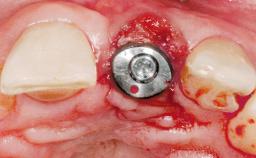

Immediate Placement of an Implant in a Maxillary Left Central Incisor Site

A 33-year-old female patient presented with an upper left central incisor that required extraction after a failed endodontic therapy. The tooth had been traumatized when the patient was a teenager and had undergone several endodontic treatments, including two apicectomy procedures. The patient was in good health and did not smoke. Clinical examination showed that the patient had a high lip line. In full smile, the gingival margins of the upper teeth were visible to the first molars. The gingival margins of central incisors 11 and 21 were only just showing. Examination of tooth 21 confirmed that the tooth was mobile and had hypererupted by 1 mm.

Placement Protocol Immediate implant placement

Tooth Site Maxillary incisor or canine

Socket Morphology Single-root socket

Socket Integrity Damage to one or more bone walls

Bone Volume Damage to one or more socket walls